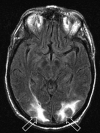

Fig 1.

Patient 1 is a 73-year-old man who developed altered mental status 11 days after orthotopic liver transplant for cholangitis and cirrhosis with blood pressure at toxicity of 140/76 mm Hg. Mild organ rejection was being treated with increased immune suppression (trough tacrolimus level minimally elevated: 21 ng/mL), and intercurrent blood culture results were positive for coagulase-negative Staphylococcus. MR imaging (FLAIR sequence) obtained at toxicity demonstrates cortex and deep WM vasogenic edema in the occipital region bilaterally (open arrows) judged Edema grade 3. Follow-up MR imaging 1 month later demonstrated complete resolution of the vasogenic edema.